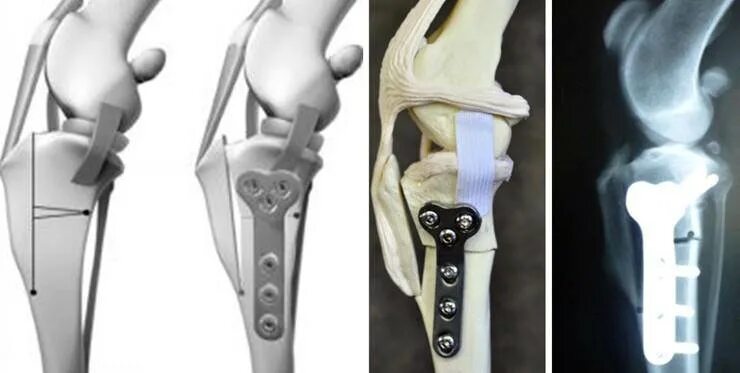

Операция суставов собак